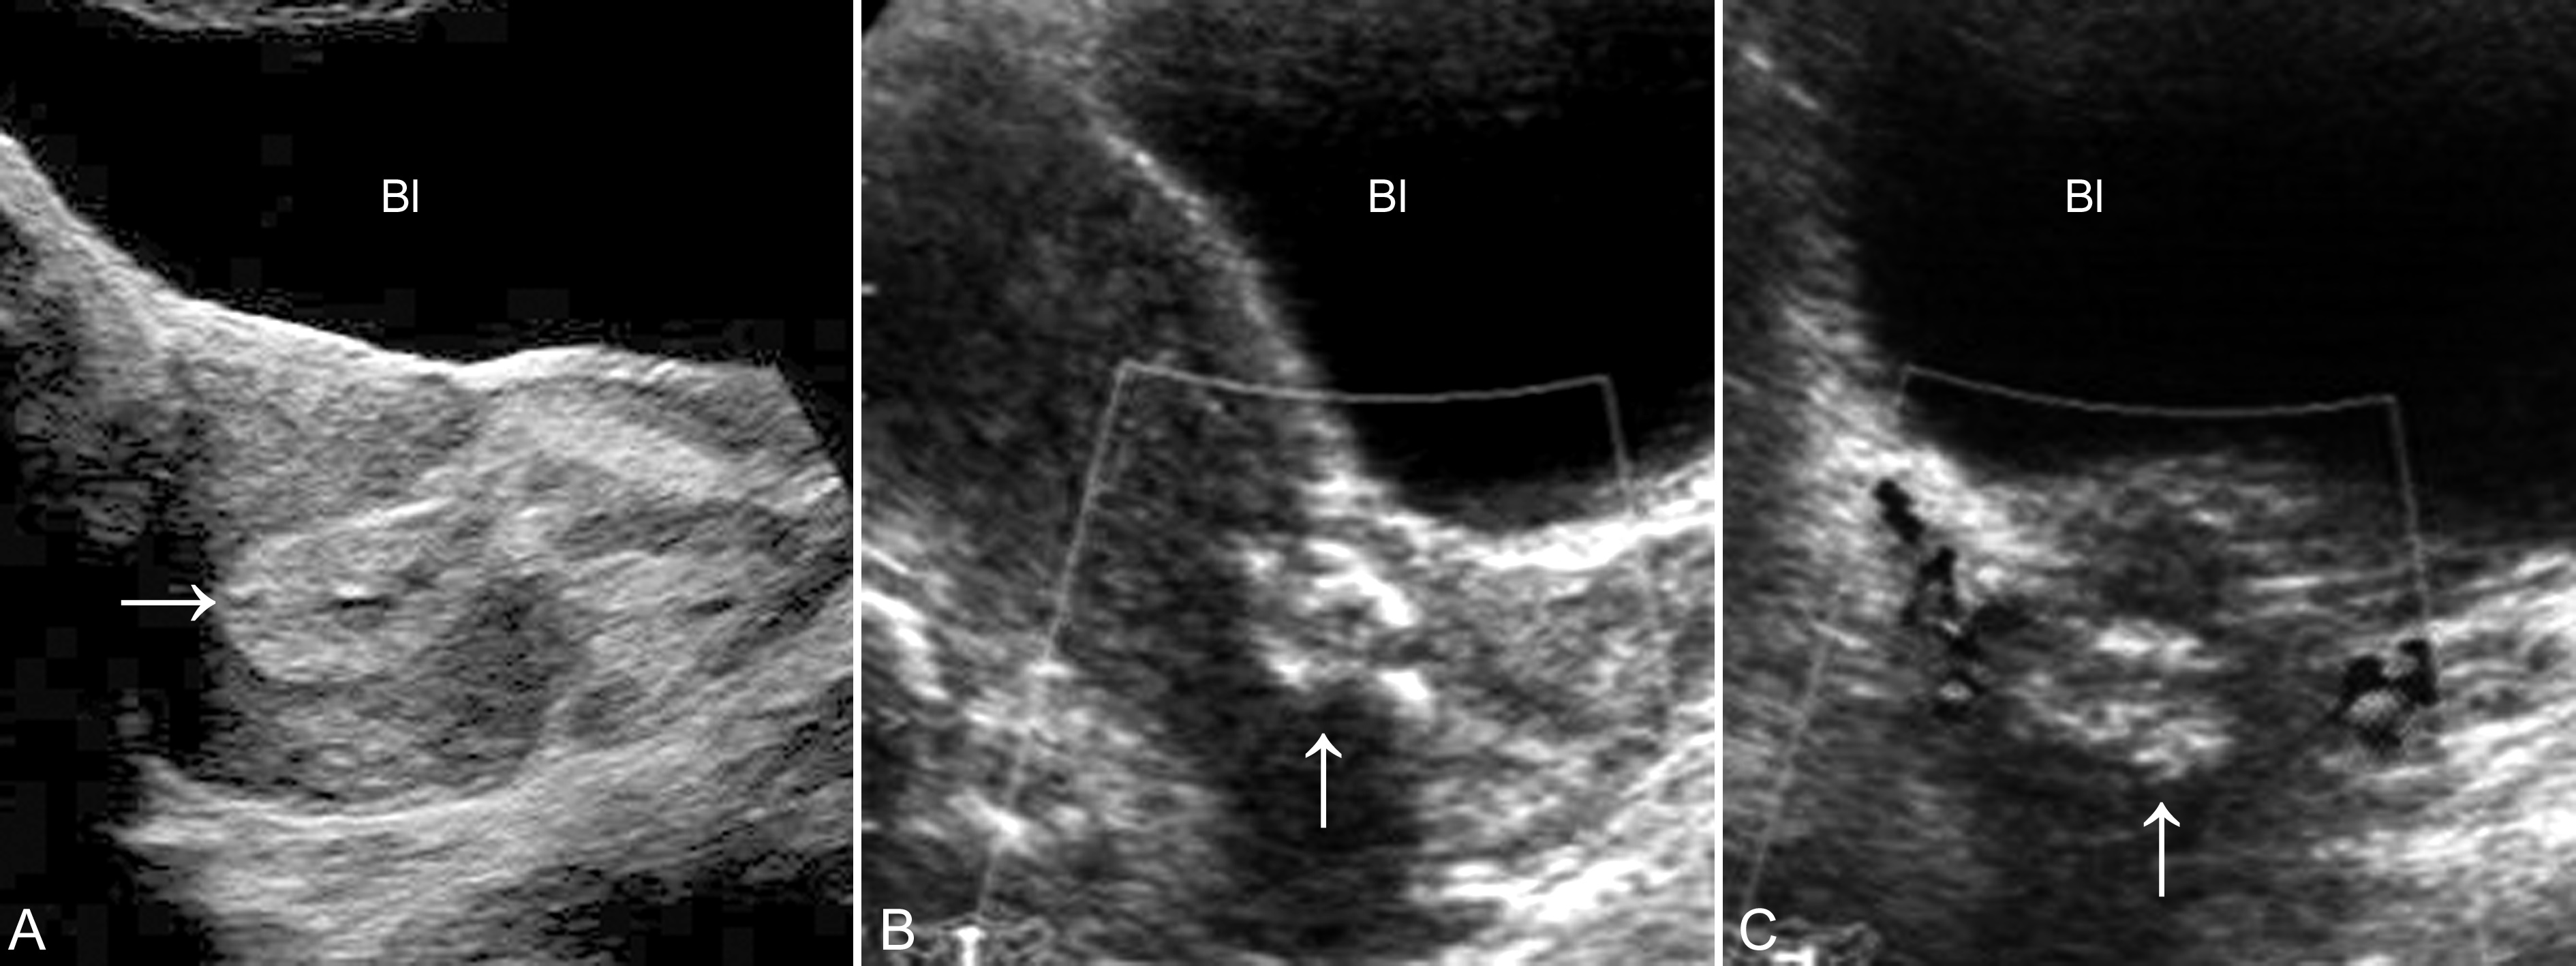

妊娠早期阴道流血是产科临床常见的症状。胚胎或胎儿的存活与否决定着临床处理方法的选择。超声显象检查可以显示妊娠囊形态、位置及其内部胚胎或胎儿是否存活等情况,为临床选择处理方法提供可靠的依据。诊断时应当注意与葡萄胎、异位妊娠、子宫内膜骨化症等疾病进行鉴别。葡萄胎和异位妊娠的声像图表现见有关章节。子宫内膜骨化症是一种比较少见的疾病,多由流产后或分娩后部分胎盘或胎膜残留、钙化后形成。在临床上,病人常有流产史或异常分娩史。超声显像检查显示子宫大小、形态正常,宫腔内可见伴有声影的强回声,单发或多发,形态不规则(图5)。回声与不全流产时的胎儿骨骼残留相似。但追问病史,病人无近期阴道流血史,无腹痛及妊娠反应等。

图5 子宫内膜骨化症声像图:箭头示宫腔内可见强回声,深部伴声影